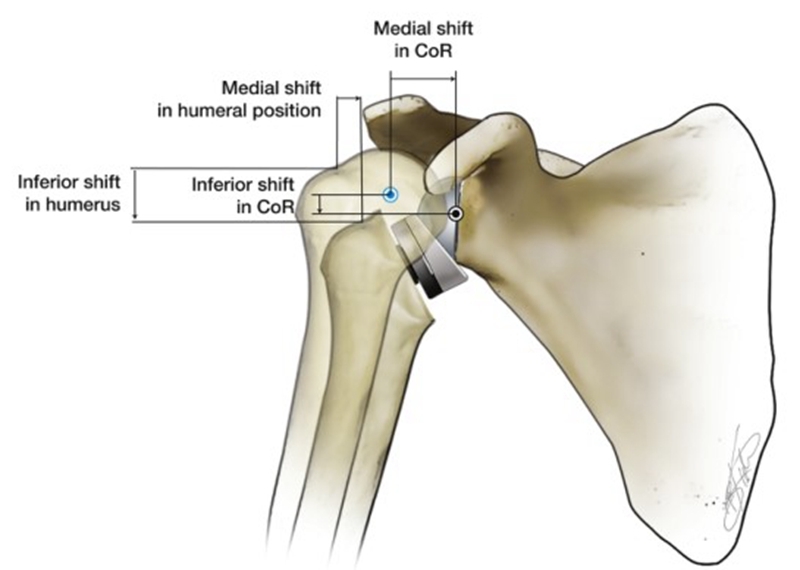

反式肩关节假体的设计原理

反式肩关节置换术(RTSA)可翻转自然肩的解剖结构关系,以恢复肩关节的稳定性。RTSA通过使关节盂侧凸起,肱骨头侧凹陷,以此来创建一个支点和旋转中心(Center of rotation,CoR)。当三角肌收缩从而外展上臂时,该支点的生物力学作用便是防止肱骨头上移。RTSA特点便是让人工肩关节的旋转中心及肱骨头相对于自然肩的位置内移和下移,不同的RTSA假体设计有所不同,CoR分别下移5~10 mm及内移20~30 mm,肱骨头分别下移25~40 mm及内移5~20 mm[3][4]

相对于人体自然的肩关节而言,内移CoR有一个显而易见的优点是三角肌的外展力矩臂从10mm增加到30mm,从而提高了三角肌的外展效率,更少的肌肉力量便可以产生相同的扭矩,而这一特点也让肱骨头的外展动作不再完全依赖于完整肩袖的下压功能[5]